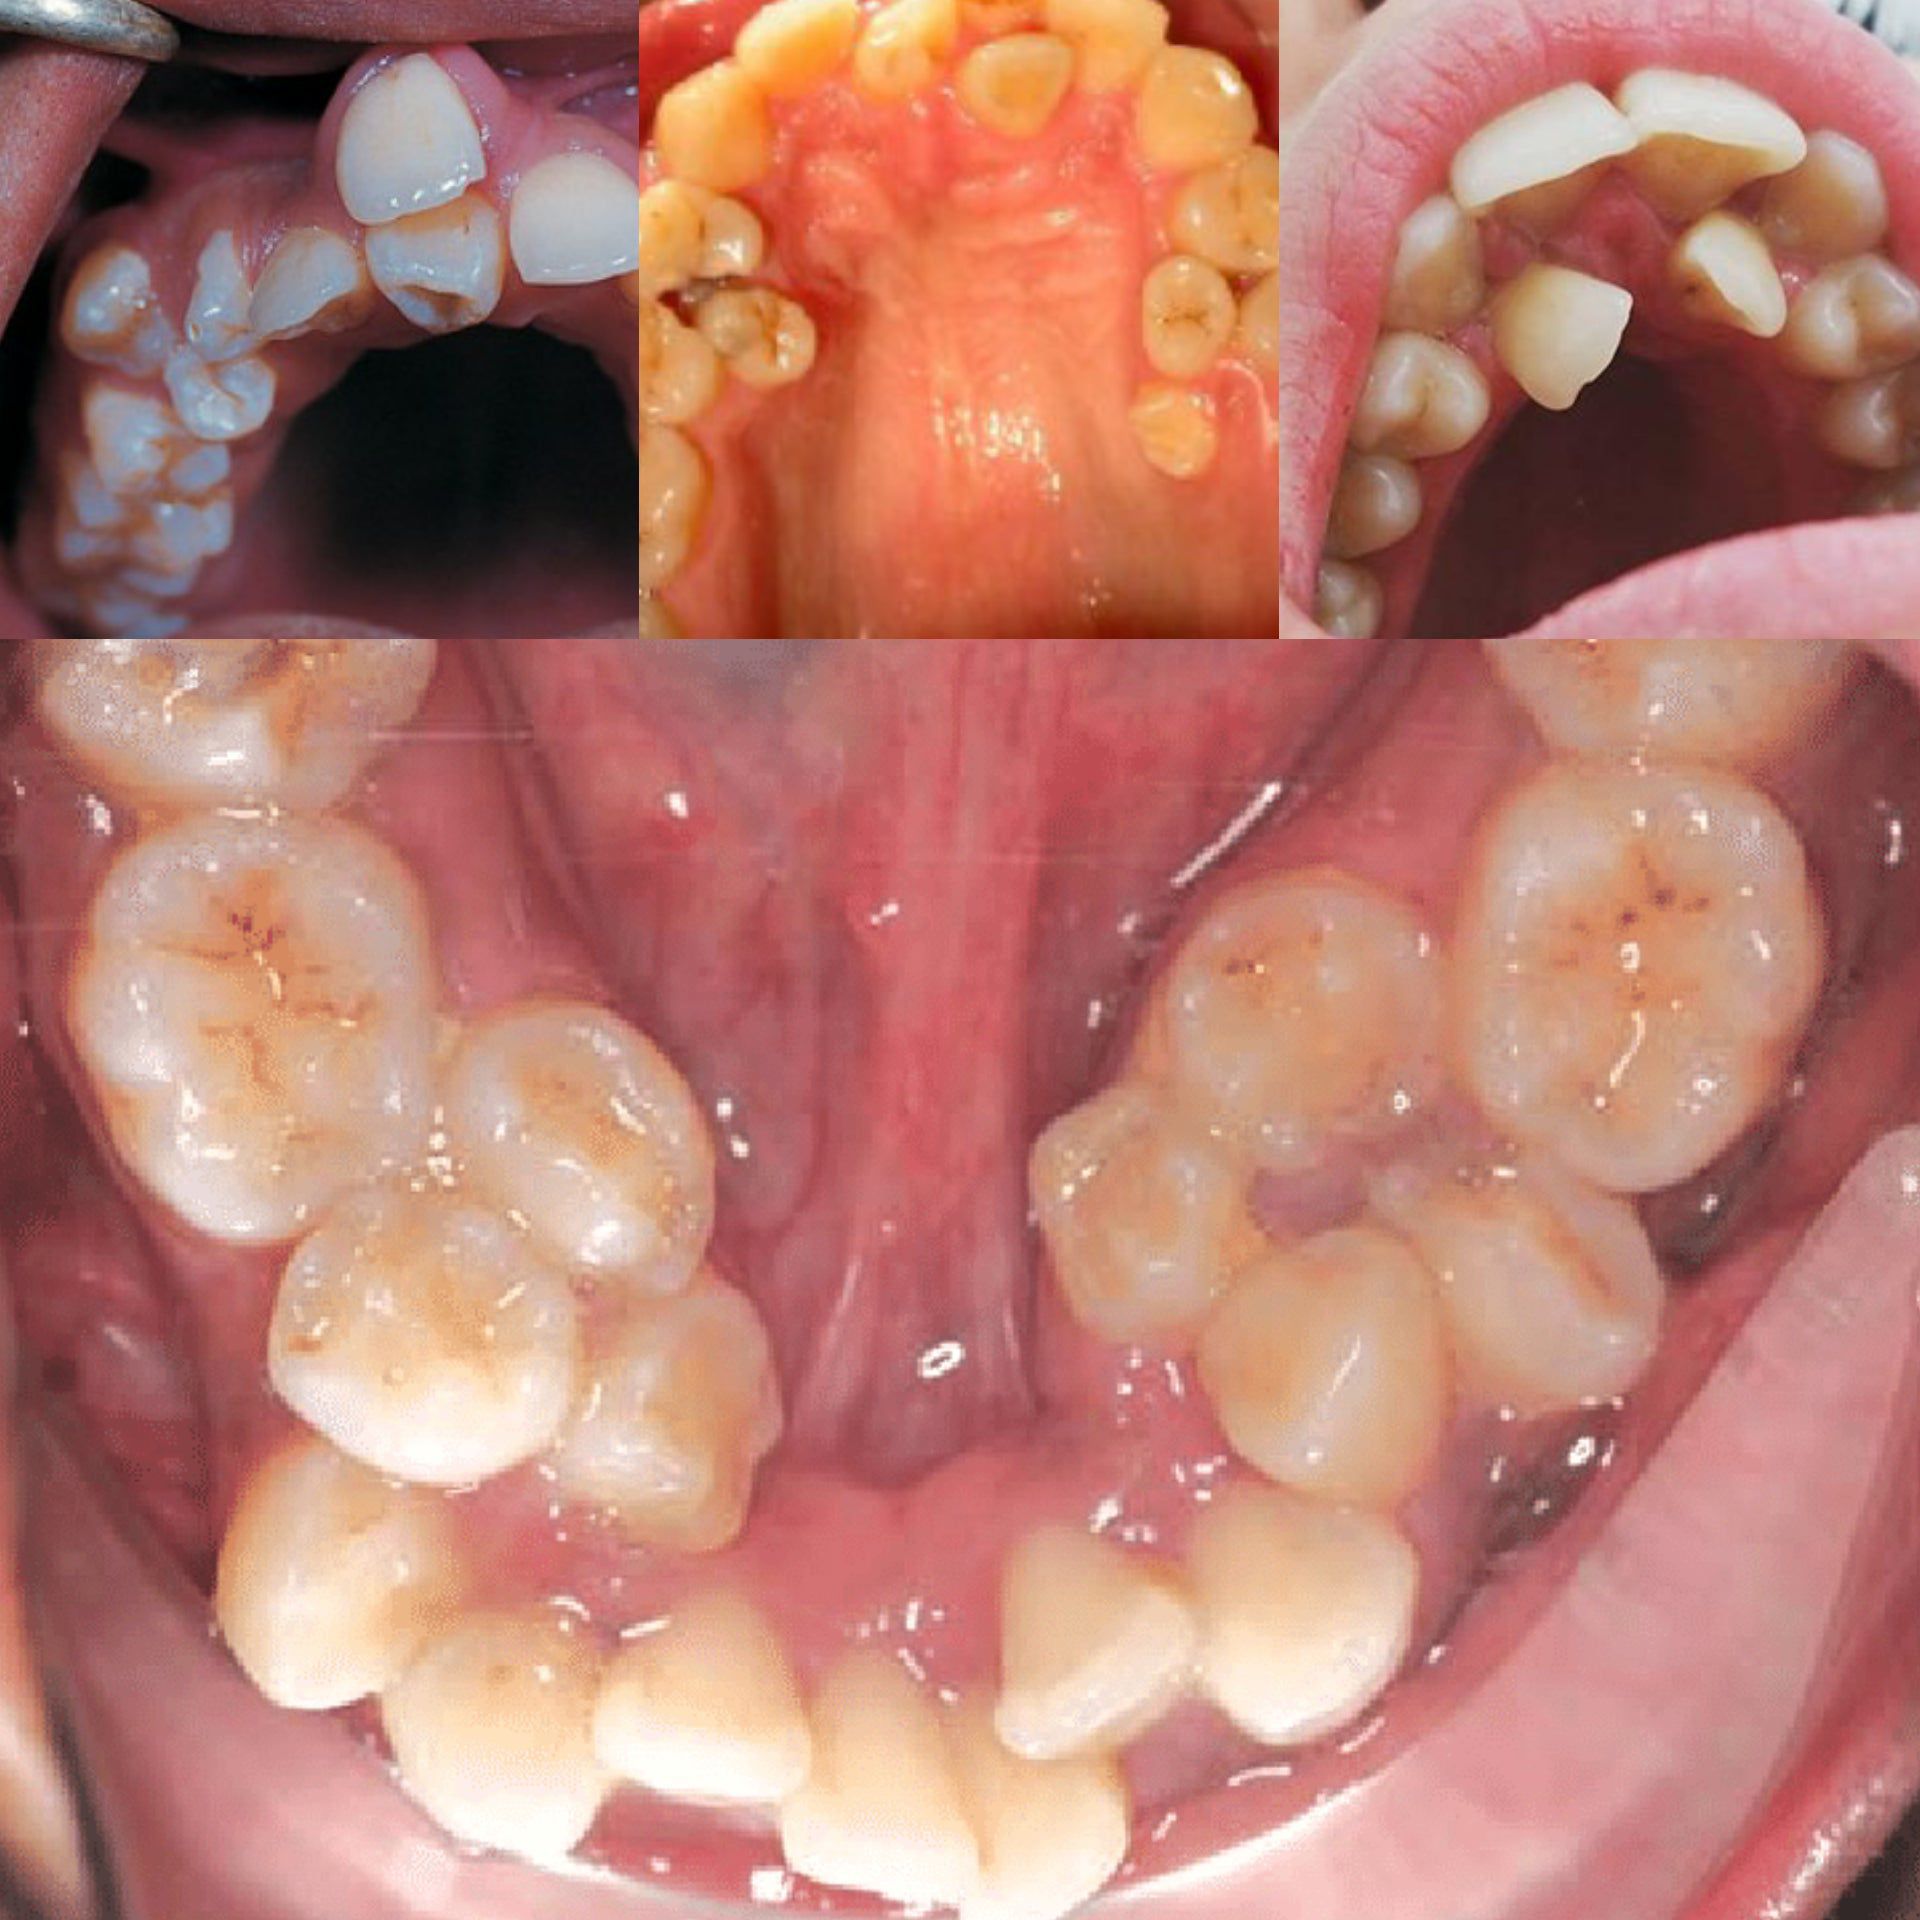

Hyperdontia

You have two sets of teeth in your life. As a child, you have 20 primary or baby teeth. These teeth fall out, and 32 permanent, or adult, teeth replace them. But some people end up with more than 32 teeth. This is known as hyperdontia.